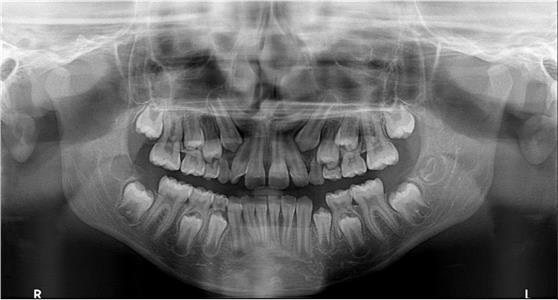

За само 13 секунди се добива високо квалитетна ортопантомграфска снимка, странична смнимка, снимка на вилични зглобови, снимка на синуси. Најновиот Kodak панорамикс има 2Д+ програма со која се добиваат 5 пресека во длабочина за прецизна дијагноза и позиција на импактирани заби и други промени. Со квалитетна панорамска снимка нашиот стручен тим ќе постави точна дијагноза и одреди соодветен план на терапија.